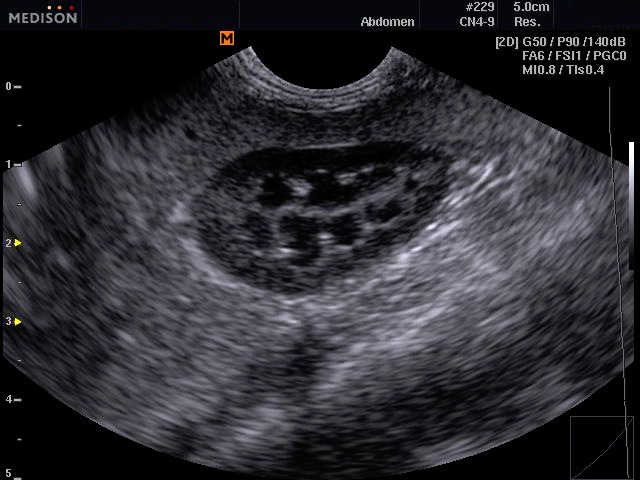

A készülék kapható állatorvosi vizsgálatokhoz szükséges vizsgálófejekkel kisállatok és nagyállatok vizsgálatához az ehhez szükséges optimális frekvenciatartományokkal.

Egyes készülékek rendelkeznek kisállat és nagyállat biometriás táblázatokkal és testábrákkal is a dokumentáláshoz.